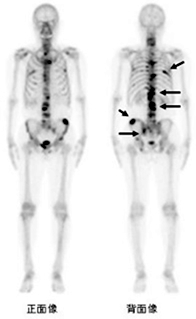

骨シンチグラフィ

- RI静脈注射をした3時間後に、全身を正面と背面の2方向からガンマカメラで撮像し、骨の無機質の代謝を画像化します。この検査で使用する放射性医薬品(99mTc-MDP)は、骨の代謝や反応が盛んな場所に集まる放射性医薬品で、骨の腫瘍や骨折・炎症の診断ができます。特に、単純X線などで診断できない骨転移を、一度に全身検索することが可能です。そのため、骨転移が疑われるときや、骨転移の治療の経過を見るときに利用されております。

- X線写真では、骨のCa含量が30~50%増減しないと診断が困難です。一方、骨シンチグラフィでは、骨の無機質(基本組成はハイドロキシアパタイト)の代謝を画像化するため、病変の検出はX線写真より早期に可能です。また、全身を撮像するので、想定外の部分への転移を検出できます。適応は、悪性腫瘍の骨転移検出、骨折・骨髄炎・無菌性骨壊死などの早期診断、代謝性骨疾患※ の治療経過観察です。中でも骨転移に対する評価と骨折の検出は、X線写真の検出率を遥かに上回るため、効果的です。